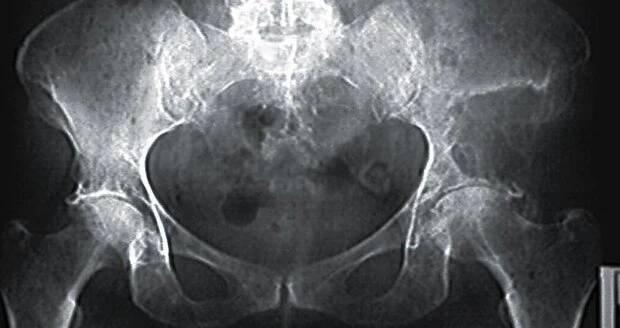

Kyčelní kloub je největší kloub v lidském těle a je tvořen spojením kosti stehenní s kostí pánevní. Je to kloub jednoduchý, tedy složený pouze ze dvou kostí, ale díky silným vazům, které kostní spojení obklopují, zároveň také nejpevnější.

Náhrada kyčle patří v současné době k nejčastějším operačním výkonům v ortopedii. Je metodou volby u pacientů s pokročilým stupněm artrózy (III. a vyšší stupeň), po zlomeninách krčku a nekrózy hlavice stehenní kosti.